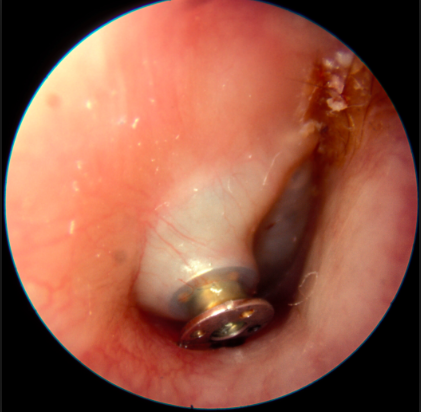

2. QUIRÚRGICO: TIMPANOCENTESIS, MIRINGOTOMÍA

1. QUIRÚRGICO

1. Tubos ventilación c/s adenoidectomía

1. >3m, bilateral, >6m unilateral.

1. Timpanoplastia c/s mastoidectomía